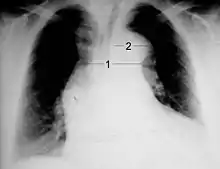

Chest X-ray

Chest radiography may although demonstrate a change in the morphology of the thoracic aorta which can be seen in aortic dissection. Classically, new widening of the mediastinum on radiograph is of moderate sensitivity for detecting an ascending aortic dissection; however, this finding is of low specificity, as many other conditions can cause apparent widening of the mediastinum.

There are several other associated radiographic findings:

- The "calcium sign" describes an apparent separation of the intimal calcification from the outer aortic margin by greater than 10 mm.

- Pleural effusions, more commonly in descending aortic dissections, and typically left-sided.

- Other: the obliteration of the aortic knob, depression of the left mainstem bronchus, loss of the paratracheal stripe, and tracheal deviation.

Importantly, about 12 to 20% of aortic dissections are not detectable by chest radiograph; therefore, a "normal" chest radiograph does not rule out aortic dissection. If there is high clinical suspicion, a more sensitive imaging test (CT angiogram, MR angiography, or transesophageal echo) may be warranted.